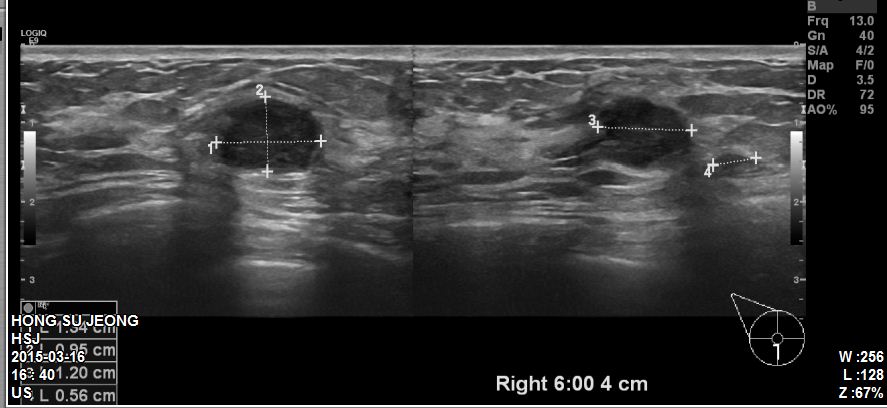

본원에 내원하신 40대 환자분이십니다.

유방초음파 시행 후 우측 6시방향에 혹 조직검사 시행하였고

침윤성유관암 진단되었습니다.